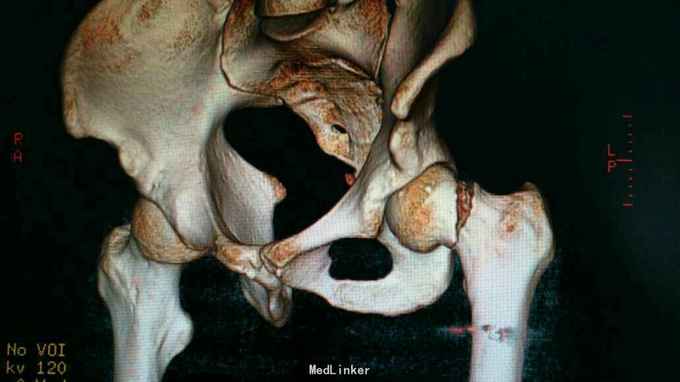

24岁男性,运动中摔倒致左髋疼痛活动受限,

左髋部压痛,大粗隆扣痛,下肢杆力消失,x光及CT证实左股骨颈骨折